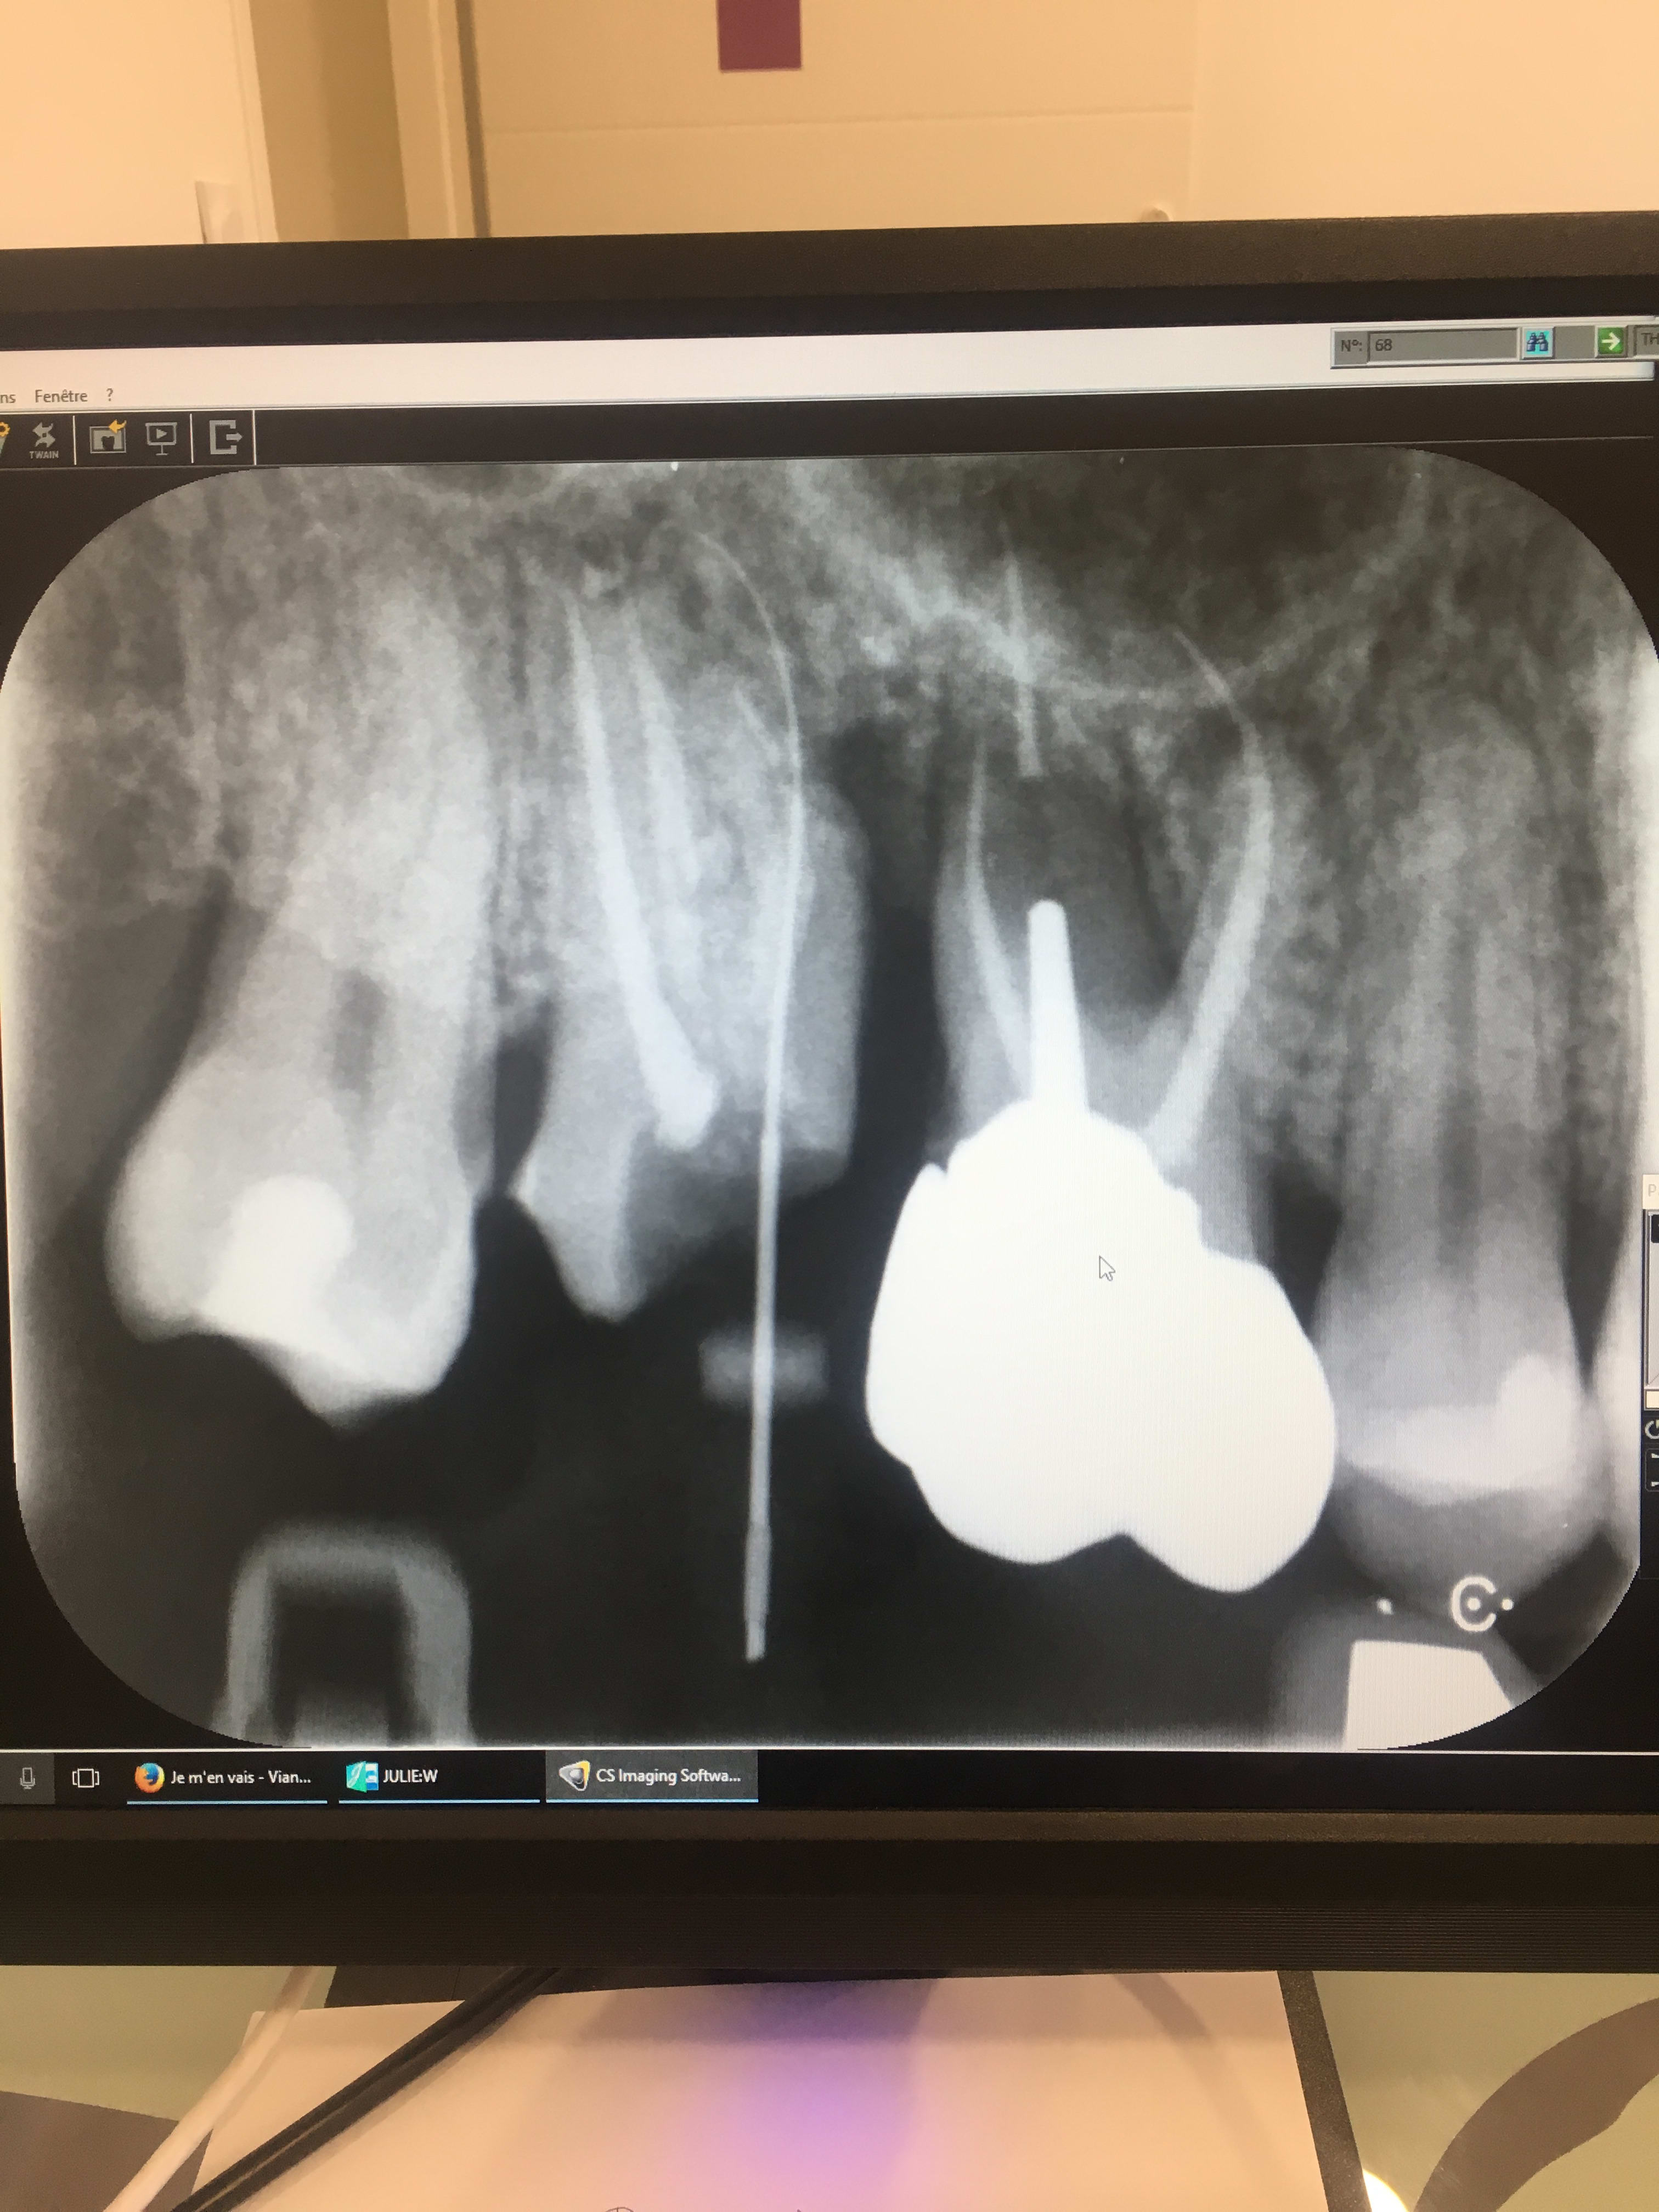

A la déposé, je m'aperçois qui a de gros tassements alimentaires entre 16 et 17 avec présence d'une poche de 12 mm en mésial de la 17 et en distal de la 16. A la radio, je suis un peu perdu. J'ai l'impression d'une résorption de la 16. Mais je n'en suis pas sur. Pouvez vous m'éclairer sur l'origine de cette lésion? S'agit il d'une lésion endo-paro? Y'a t il résorption de la 16? J'ai l'impression qu'il y a une fracture de la racine mésiale de la 17. Bref je suis perdu?

la 16 c'est soit une carie radiculaire, soit une résorption...mais çà ne changera rien au pronostique...exo

la 17, tu as une perforation et de toutes façons il y a un instrument pété à l'apex avec lésion apicale...donc exo là aussi...

pour ce qui me concerne je vire 16, je vire rac M 17 , je réevalue le reste de 17 (qui me paraît recupérable)

alors là, je demande à voir...mais la lésion apicale qui englobe tous les apex de la 7 lié à une poche paro très profonde...pour moi c'est exo...